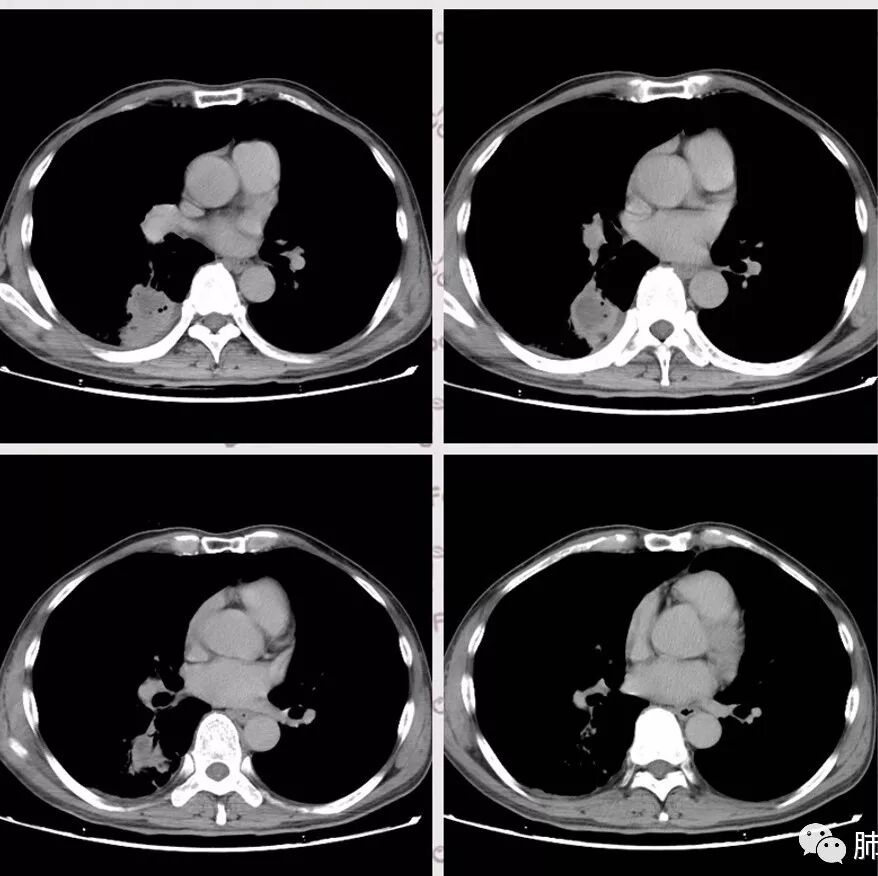

右肺下叶团块状密度增高影,边缘模糊,其内见液性低密度影,多发小气泡影及充气支气管征,考虑肺脓肿。颅内双侧顶叶长T2长T2病灶,周围水肿,DWI高信号,增强扫描囊壁环形强化,囊壁钙化,周围水肿,考虑脑脓肿。患者长期接触垃圾,什么菌都有,肺、脑脓肿,考虑肺克。再有肝脓肿就更支持了。

慢性病程,体质一般、接触垃圾,右下肺长轴与胸膜平行肿块,近肺门侧液化坏死伴多个小圆型空泡,肿块密度不均、不均匀强化,周围少量胸膜增厚,脑内多发空洞灶,考虑肺脑脓肿。鉴别肺腺癌脑转移。

胸部CT:右肺下叶背段实变,广基底,糊墙,长轴与胸膜平行,周围晕,支气管进入堵塞,纵隔窗可见低密度坏死,实变内小空洞?脑部不会看。

胸CT:右肺下叶背段实变影,内可见小空泡,病灶与胸膜呈宽基底,实变病灶周围存在毛玻璃影,纵隔窗可见病灶内存在低密度,增强可见病灶强化,并见病灶内低密度区。头MRI不会看。

右肺下叶背段实变,广基底,糊墙,长轴与平行胸膜,周围有晕,支气管进入堵塞,可见低密度坏死及小空泡。颅内多发环形强化灶,符合脑脓肿三层结构,结合临床,考虑:感染性病变,隐球菌?鉴别肺克。

肺内类三角形稍高密度病灶,边缘模糊,其内看见两个小气泡影。增强扫描欠规则厚壁中度强化,其内有轻度强化或未强化区。符合肺脓肿表现。

右肺下叶见不规则软组织影,边缘不清,内夹杂气体,背段支气管未见明显阻断,增强扫描下叶病灶内见类圆形低强化区,其边缘光滑,见低强化区壁,颅脑左侧枕叶及双侧顶叶见多发长T1长T2信号,T2高信号内见类圆形异常信号,壁呈低信号,DWI环形壁未弥散受限,内容物弥散受限,周围为水肿区,增强扫描呈多发环形强化,考虑血源型感染,颅内及右肺下叶脓肿形成

右肺下叶大片实变

我们回头看肺内的,病灶位于下叶背段,可惜没重建

近肺门区见一坏死腔,内壁较清楚,空泡在周围

单从这个坏死我们分析:1、炎性?2、鳞癌?

厚薄均匀,强化一致,未见壁结节,坏死位于病灶近端,我会首先考虑炎性

局部部分边缘膨隆,欠光滑

不是单纯的近端堵塞,远端不张,远端实变,宽基底

远端实变区膨隆,部分似有栽赃的趋势

感染一定有,但是应该还有警惕癌

南边:

一般来说炎性空洞坏死,空洞偏内的结核多,癌性空洞一般是远端的缺血坏死,这个病例特殊,近端支气管显示不清,内壁部分清晰,部分不清晰,是不是层厚的问题?

炎性有。从总体来说,病变分两部分,靠肺门这里是一个弧形的。从影像来说,确实有些壁不是很清楚,层厚、窗宽窗位影响,这个壁细节显示不是那么清楚。大点病灶是一个有分叶的,宽基底在外侧,病灶边缘有膨隆的迹象。

2.影像右肺下叶大片高密度影,整体边界模糊柔和,中央见圆形液化区及微小气泡影,内壁相当光整,环形强化,未见明确壁结节。双肺门及纵隔未见增大淋巴结。这样的病灶更符合细菌性肺脓肿,以肺炎克雷伯杆菌感染最为常见。